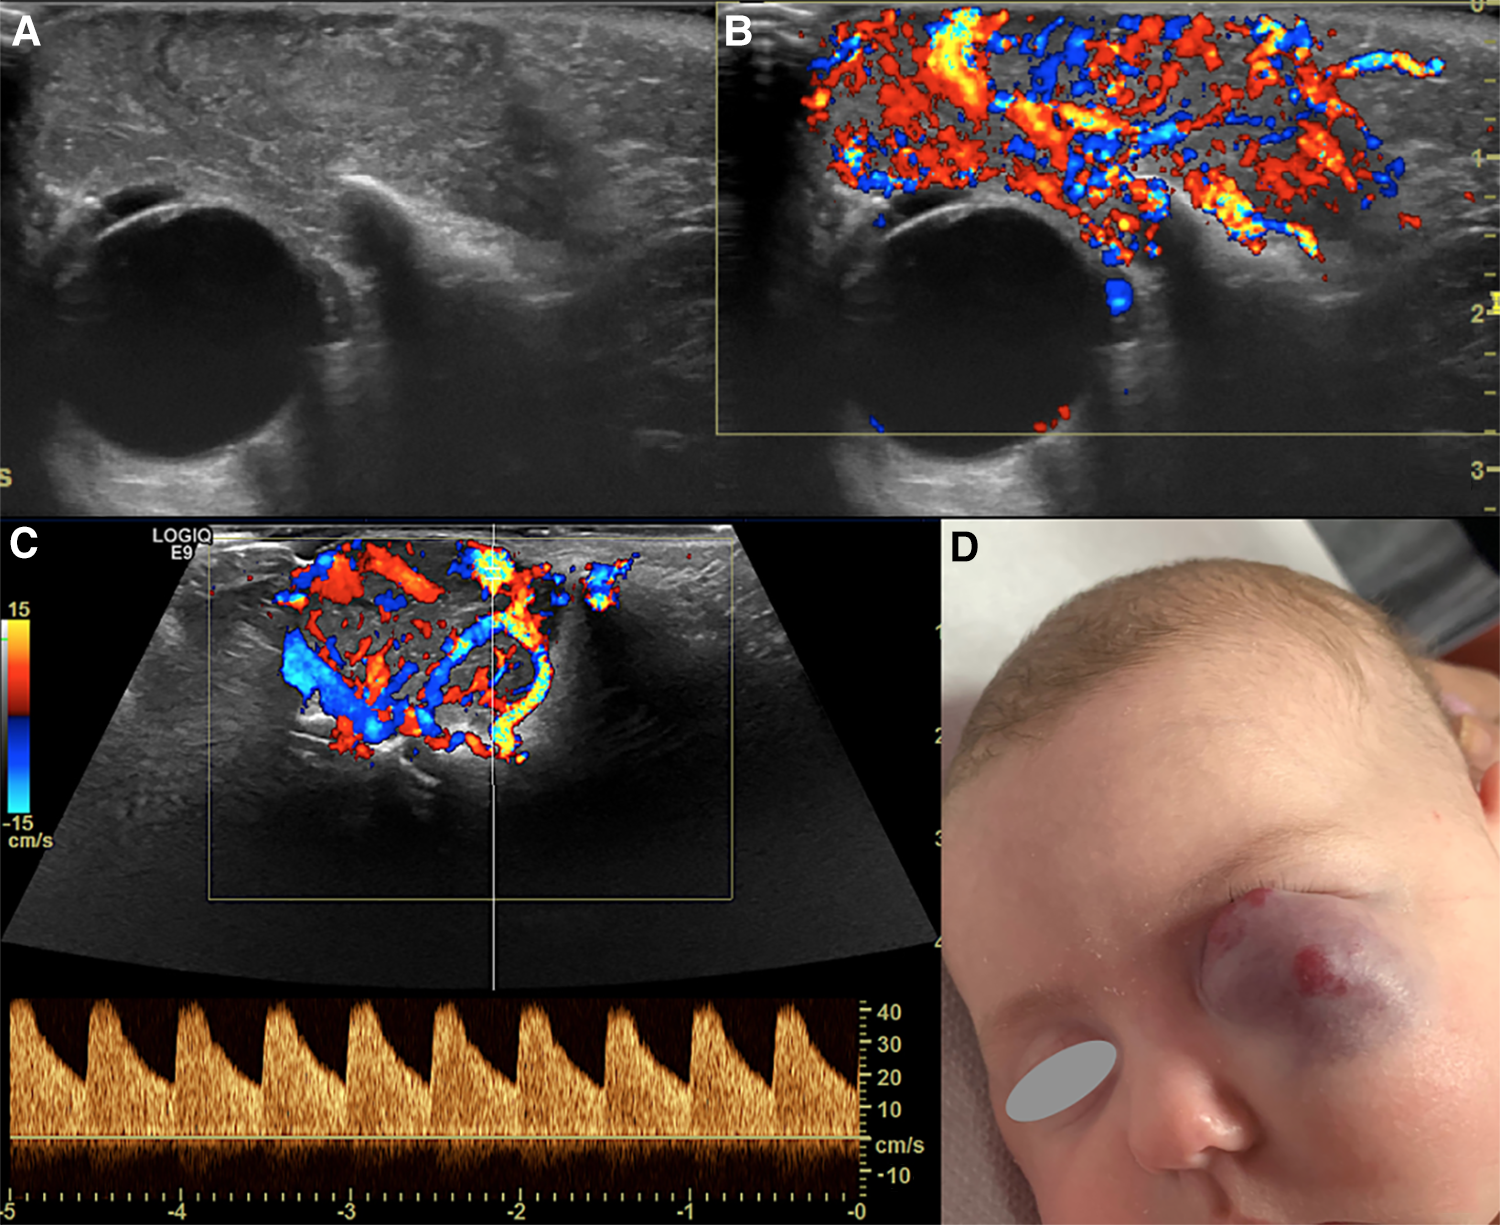

Figure 2. Us of an infantile hemangioma (IH) of the left orbit in a 5-month-old boy, during the proliferative phase. B-mode US shows a hyperechoic mass with well-defined margins overlying the globe (A) and a very high vascular density at Color-Doppler US (B). Spectral analysis revealed the presence of low resistance arterial flow (C). The clinical appearance of the lesion is depicted in (D).

Despite the different pathogenesis, clinical presentation and genetics, CH and IH have almost the same imaging characteristics, particularly during the proliferative phase. However, CHs are more likely to have aneurysms, larger venous components, intravascular thrombi and even high flow velocity at birth, compared to their infantile counterpart (19), ancillary findings that must be carefully be searched for. US demonstrates a well-demarcated tumor with variable echogenicity and high vascularity, showing more than 5 vessels/cm with high flow velocities at Color Flow Doppler during the proliferating phase (20) (Figure 2). During the involuting and involuted phases, flow velocity and vessel density will decrease. Due to its considerable abilities in the assessment of intra-lesional blood flow, CEUS is making its way as a powerful additional tool in the assessment of orbital space-occupying lesions (21, 22). At CEUS hemangiomas are hyper-enhancing during both the early and late arterial phase. Enhancement of IHs starts as a peripheral nodules and then progressively expands in a centripetal pattern and completely fills the lesion (Figure 3). During the delayed phase, hemangiomas keep showing sustained enhancement relative to surrounding tissues.